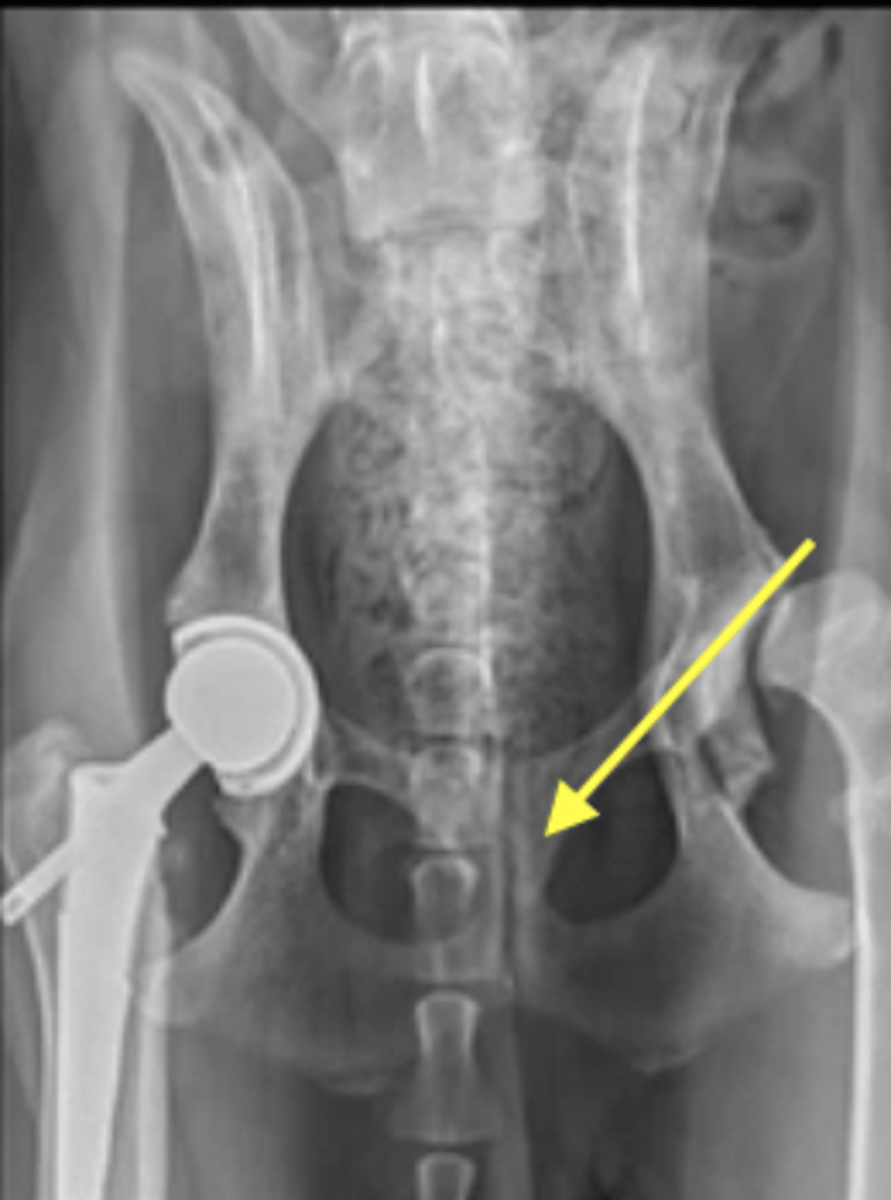

hind limb

What does the "H" label on this image indicate?

front limb

What does the "F" label on this image indicate?